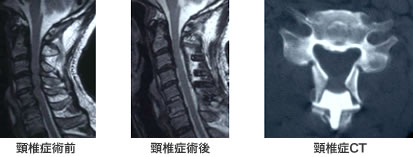

手術は、前方からもしくは後方から行います。いずれから行うかは、病変部分がどこにあるかにより決まります。左図は、後方より椎弓形成術を行った頸 椎症の術前MRIです。中図は頸椎症の術後MRIです。脊髄神経が十分に除圧されています。右図は術後CTです。観音開きにされて、セラミック製の人工の 骨をはさんで、脊柱管を拡大しております。